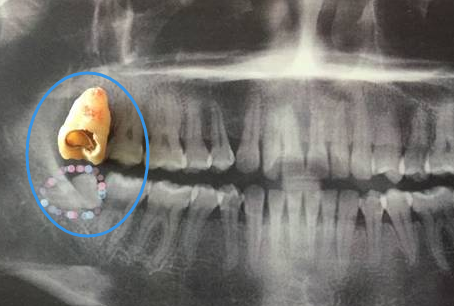

一般智齒長歪了經常發炎需要拔牙,牙齒齲壞嚴(yan) 重無法保留需要拔牙,牙齒嚴(yan) 重鬆動需要拔牙....隻要是牙齒沒法正常保留使用的牙齒都是需要拔牙的,那麽(me) 拔牙過程中到底疼不疼呢,接下來介紹一下。...

根據大部分**拔牙的具體(ti) 情況得知:拔牙過程中還好,隻有一點點痛,就是在打麻醉的時候那一會(hui) 兒(er) ,過了就全程沒有感覺了。雖然可以感受到醫生的操作,但是沒有不舒服和難受的情況,可能會(hui) 有緊張的情況,建議放鬆心情。所以這就是局部麻醉的結果,大家是不用擔心醫生拔牙的時候會(hui) 疼痛的。

而且大家反映比較強烈的是拔牙後很疼!這是因為(wei) 拔牙後麻醉藥效過了,所以創口會(hui) 開始腫脹疼痛,一般拔牙當天如果使用冰袋冷敷,可以適當止痛和緩解,但是在第二天和第三天也是有腫脹和疼痛的,可能會(hui) 更為(wei) 嚴(yan) 重,需要根據醫生醫囑,吃一些消炎止痛藥物,這樣可以緩解一下,一般在第4天就會(hui) 好轉。

以上是智齒拔牙疼痛的情況,其他普通的牙齒拔除會(hui) 比較簡單,所以在疼痛等方麵也會(hui) 更輕,所以拔牙過程真的不疼,而是拔牙後疼!不過大部分人都能忍受,所以大家也可以放心。